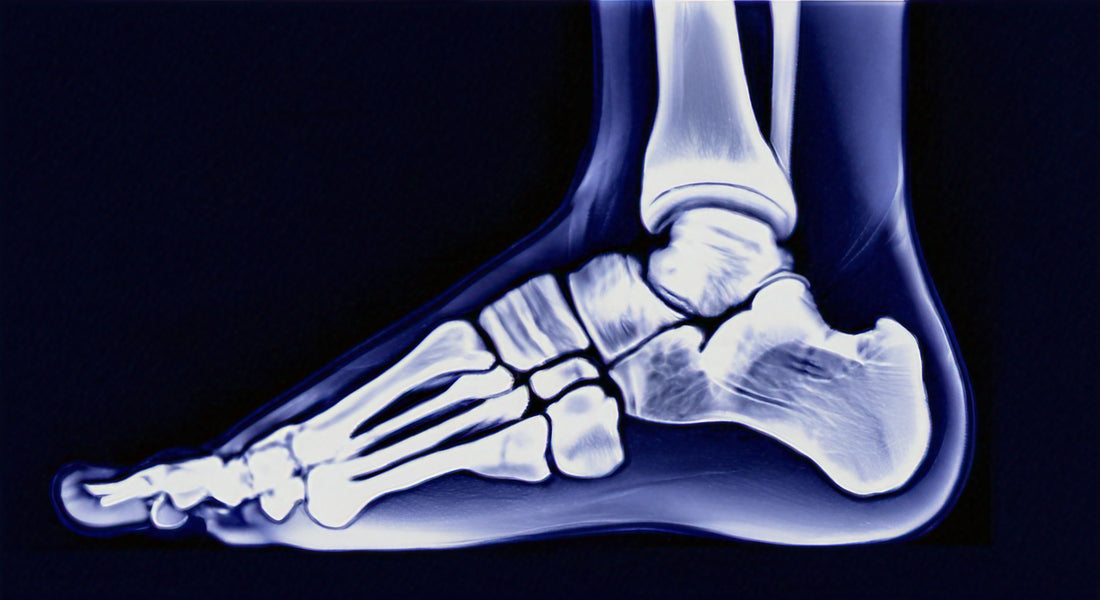

Plantar fasciitis is a common foot condition that causes pain and discomfort in the heel. It occurs when the plantar fascia, a thick band of tissue that connects the heel bone to the toes, becomes inflamed or strained.